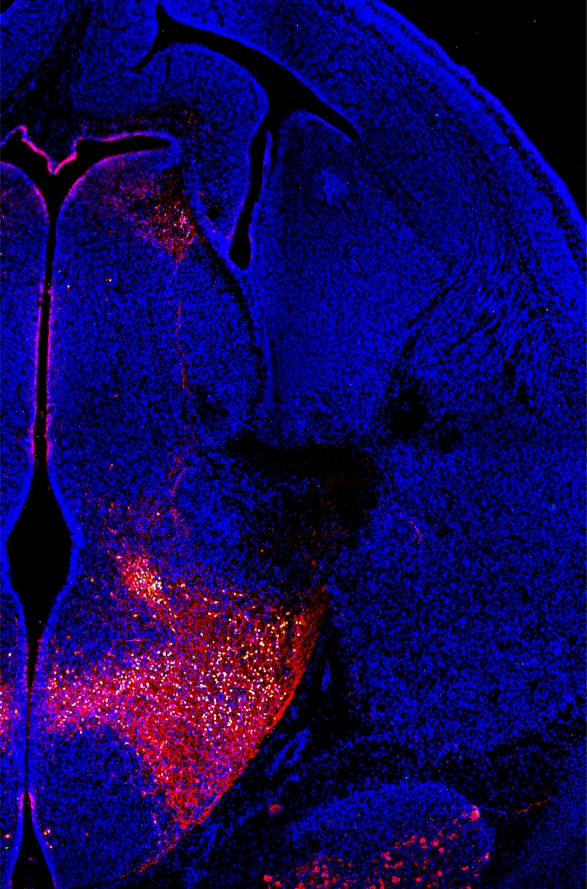

A novel population of TSH/glutamate neurons in the lateral hypothalamus

Mouse embryo with nerves, and transcription factors stained.